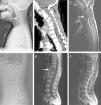

(A–C) A 35-year-old man with atypical spinal TB. (A) Lateral lumbar spine radiograph showed tumefaction of paravertebral soft tissue. (B) A sagittal T2-weighted MRI showed worm-eaten destruction of vertebral endplate at multiple vertebral bodies (T11-L1), irregular abnormal signal in paravertebral soft tissue. (C) Axial MRI showed formation of fistula at level of L2 vertebral body.